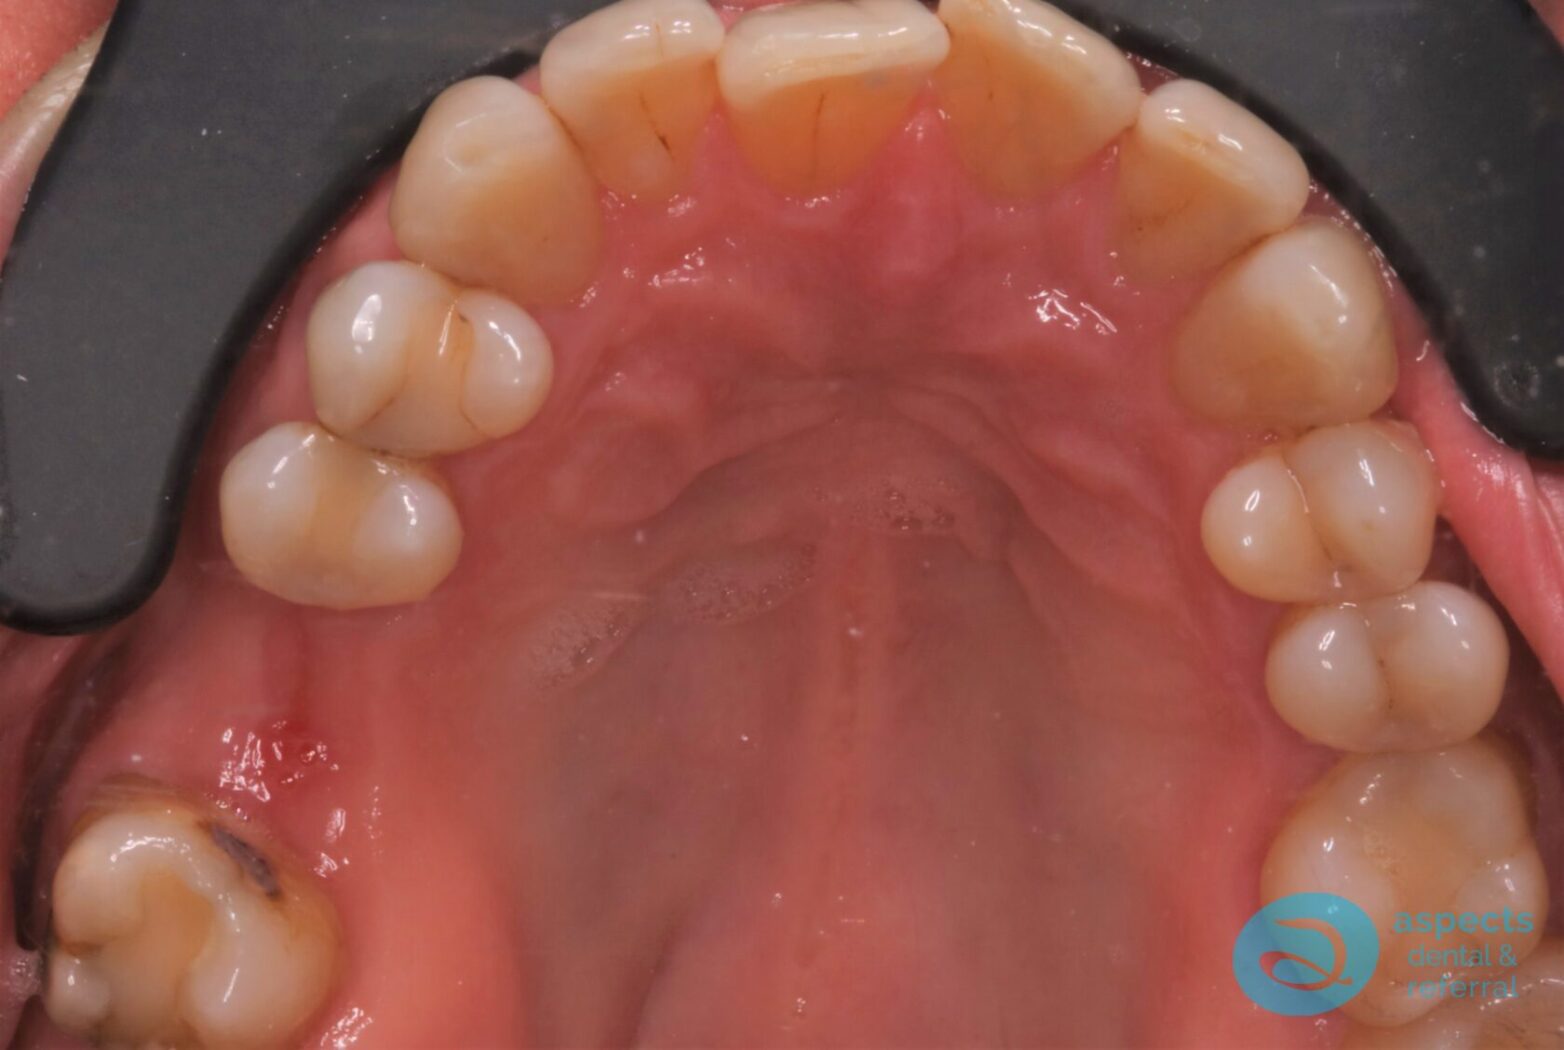

Before Dental Implant Photo